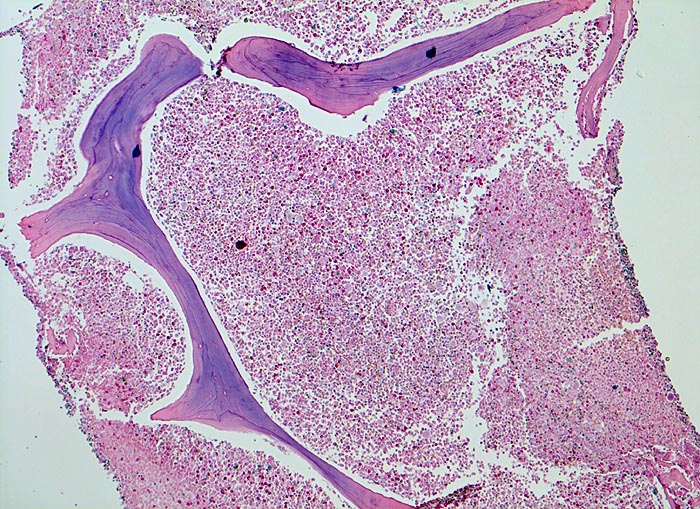

In der chronischen Phase zeigt das Knochenmark eine Hyperzellularität, welche auf eine Vermehrung der neutrophilen Granulozyten und deren Vorläufer zurückzuführen ist. Der paratrabekuläre Streifen unreifer Granulozyten kann verbreitert sein von normal 2-3 Zellschichten auf 5-10 Zellschichten. Blasten machen weniger als 5% der Knochenmarkzellen aus. Eine Blastenzahl von mehr als 10% deutet auf eine Transformation in ein akzeleriertes Stadium und von mehr als 20% entspricht einer Blastenkrise mit Transformation in eine akute Leukämie. Die Megakaryozyten sind typischerweise kleiner als normal, haben hypolobierte Kerne und sind bei 40-50% der Patienten vermehrt. Der Prozentanteil der erythroiden Vorstufen ist gewöhnlich vermindert (G:E Ratio >5:1. Die initiale Knochenmarkbiopsie zeigt bei 40% der Patienten eine Vermehrung von Reticulinfasern assoziiert mit einer erhöhten Anzahl Megakaryozyten. Das Ziel der histologischen Untersuchung des Knochenmarks besteht darin, den Anteil an Blasten im Knochenmark und damit das Stadium der Erkrankung festzulegen. Bis zu einem Blastengehalt von weniger als 10% der kernhaltigen Zellen spricht man von einer chronischen Phase, zwischen 10 und 20% von einer akzelerierten Phase und bei über 20% liegt eine akute Leukämie vor.

• Fast 100% Zellularität des blutbildenden Marks (praktisch keine Fettzellen, sogenanntes "packed marrow").

• Stark vermehrte, ausreifende Myelopoese.

• Der paratrabekuläre Saum unreifer myeloischer Zellen ist verdickt auf 5 bis 6 Zellen.

• Verdrängung der Erythropoese.